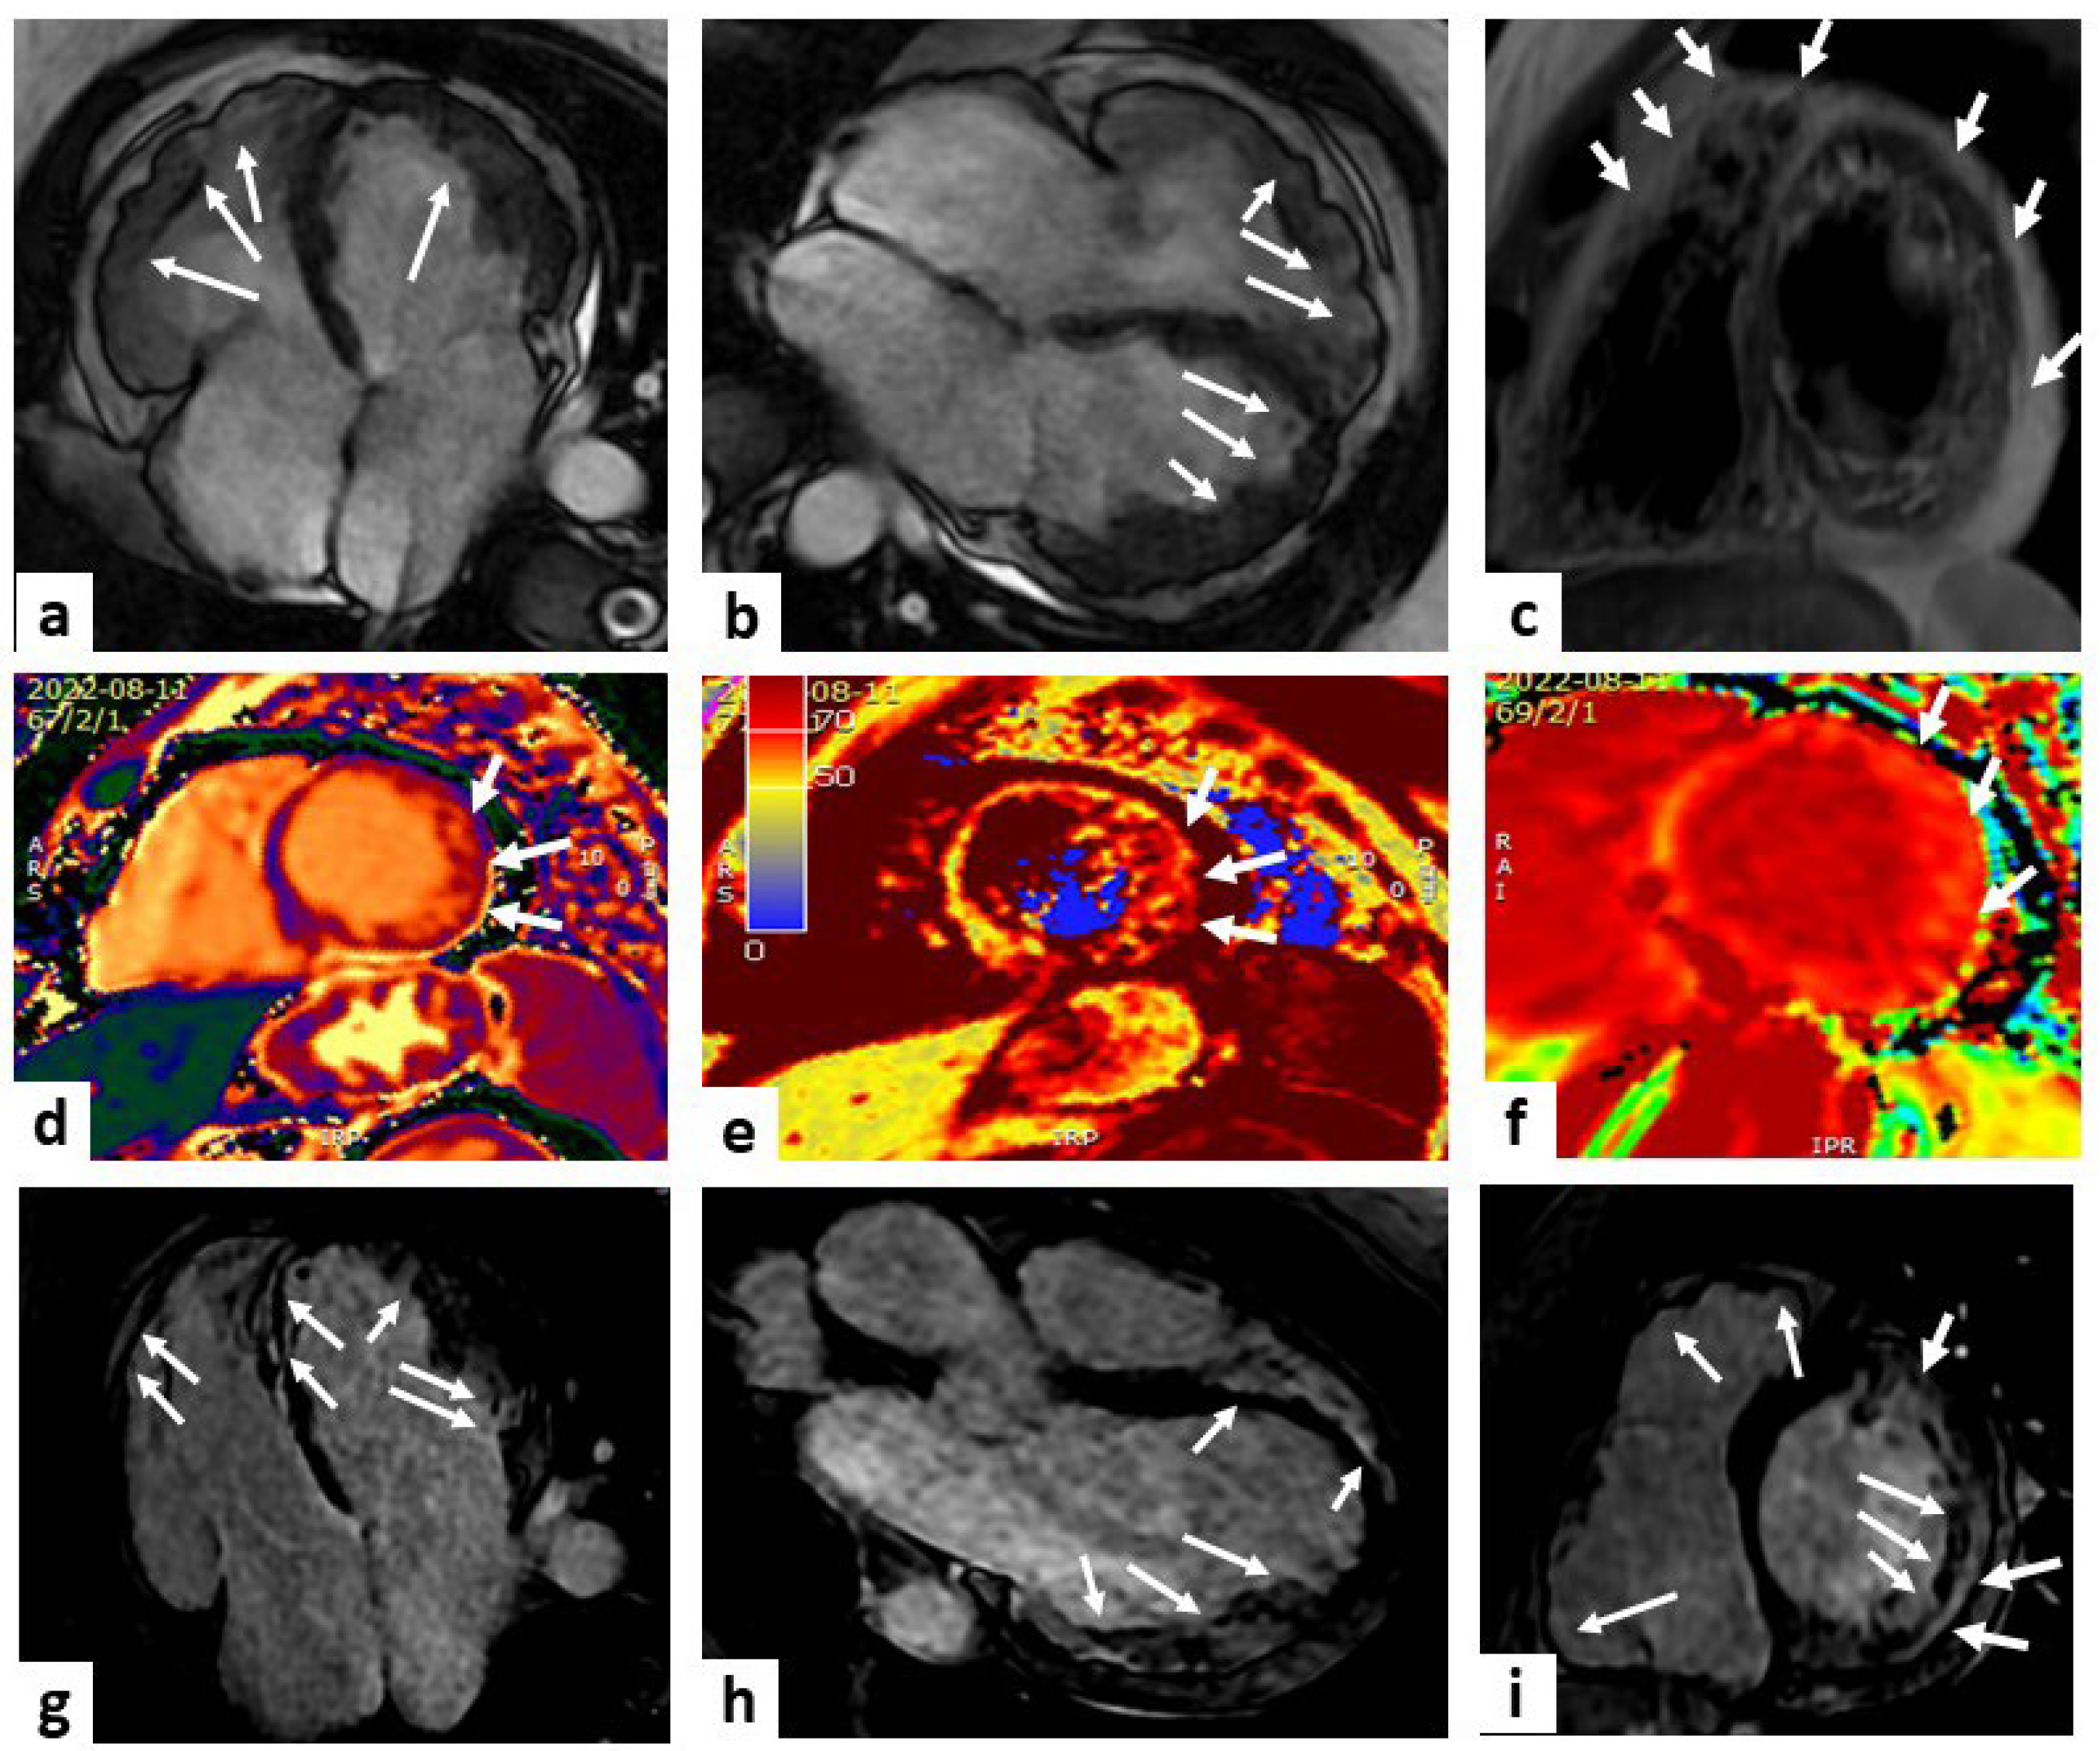

MRI is considered the gold standard in the differential diagnosis of different forms of cardiomyopathy with hypertrophic phenotype (Figure 1).

Figure 1.

Cardiac MRI of hypertrophic cardiomyopathy (HCM). A case of a 38-year-old male with a history of premature ventricular beats. Panel (a) (SSFP sequences) represents a four-chamber and short axis views (top left panel and top middle panel, respectively) showing a marked and asymmetric hypertrophy of the interventricular septum (white arrowheads). Panel (b) (TIR t2 sequence) represents a short-axis view showing a higher signal al the level of the septum (white arrowheads) compared to the remote myocardium. Panels (c,d) represent increased values on T1 mapping sequences at the level of the basal and middle septum (white arrowheads), respectively. Panel (e) represents increased values on extracellular volume (ECV) sequence at the level of middle septum (white arrowheads black outlines). Panels (f–h) (LGE sequences) display a non-ischemic pattern of hyperenhancement at the level of septum (white arrowheads). Taken together, these findings are diagnostic of asymmetric HCM.

T1 and T2 mapping helps identify areas of fibrosis, edema, and inflammation, aiding risk stratification and treatment planning. Quantitative cardiac MRI data contribute to a better understanding of disease progression and guide interventions, such as septal reduction therapies.